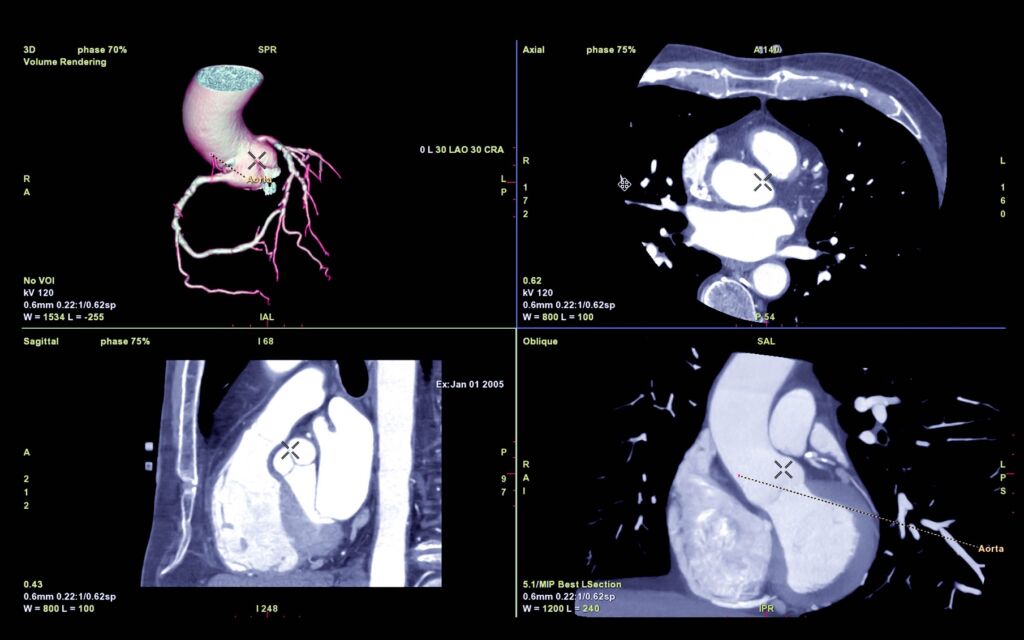

CTA Coronary artery 3D rendering image or coronary tree with axial , sagittal and coronal view for diagnosis of vessel coronary artery stenosis .